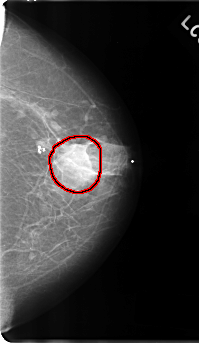

C_0177_1.LEFT_CC

LEFT_CC LINES 4816 PIXELS_PER_LINE 2784 BITS_PER_PIXEL 12 RESOLUTION 50 OVERLAY

FILE: C_0177_1.LEFT_CC.OVERLAY

TOTAL_ABNORMALITIES 1

ABNORMALITY 1

LESION_TYPE MASS SHAPE IRREGULAR MARGINS ILL_DEFINED

ASSESSMENT 4

SUBTLETY 3

PATHOLOGY MALIGNANT

TOTAL_OUTLINES 1

BOUNDARY